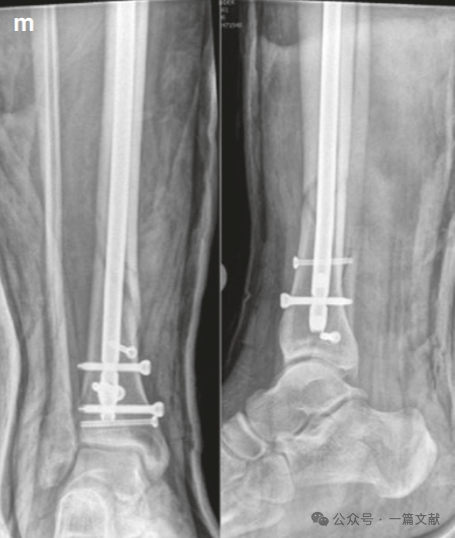

随后的阻挡螺钉被置入在髓内钉的另一侧,即拇指和手指放置在骨头上的相反侧(按压的对侧)。如下图:本例展示了仅在远端骨块(干骺端)打入两枚阻挡钉,首先在靠近骨折线的近端打入一枚阻挡钉,不足以完全纠正畸形,随后在远端骨块髓内钉对侧的远端打入第二枚阻挡钉。

8,阻挡钉技术还可用在骨不愈合病例中。这样做可以提供额外的支持和稳定性,帮助促进骨折愈合,特别是在那些难以通过常规方法达到稳定固定的情况下。保留阻挡螺钉不仅有助于维持骨折复位,还能提高整体固定结构的刚性,从而提高治疗成功率。